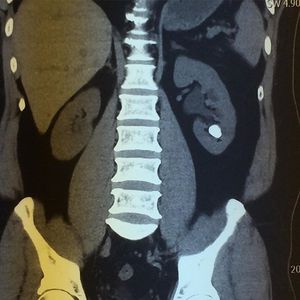

Kidney calculus

Kidney

Urology